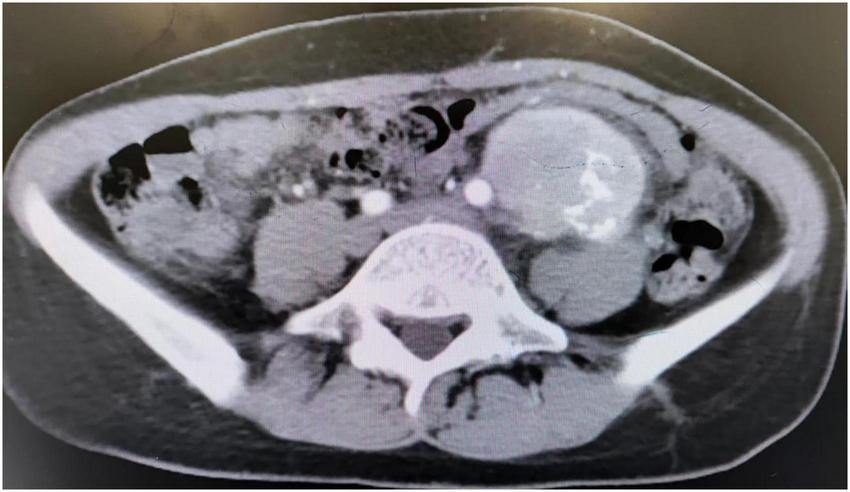

Multiple erosions were observed on the oral mucosa and tongue (Figure 1A), as well as on the fingers of both hands (Figure 1B). The physical examination of abdomen revealed no abnormal results. The abdomen was flat with no scars. There was no tenderness or rebound tenderness throughout the abdomen. A firm mass was palpable in the left lower quadrant, with a clear boundary from the surrounding tissues. A biopsy of a finger erosion was consistent with lichen planus. A contrast-enhanced abdominal CT scan revealed a solitary mass in the left lower abdomen measuring 5.4 cm × 5.1 cm × 9.2 cm, with a clear boundary from the surrounding tissues (Figure 2). The patient’s biochemical profile, full blood count, serum antibodies (IgA, IgG, and C3) and coagulation profile were normal with no significant abnormalities detected. The result of the human immunodeficiency virus (HIV) screening test was also negative. One of the tumor markers was abnormal, the squamous cell carcinoma-associated antigen level was significantly elevated at >70 ng/ml (normal range: <1.5 ng/ml). Direct immunofluorescence examination of the skin revealed a reticular deposition of IgG and C3 in the intercellular spaces of the epidermis. Histopathology of the lesions revealed lichenoid interface dermatitis. According to the diagnostic criteria established by the European Academy of Dermatology and Venereology in 2023, she was diagnosed with PNP (12).

FIGURE 2

CT scan showed an abdominal mass.